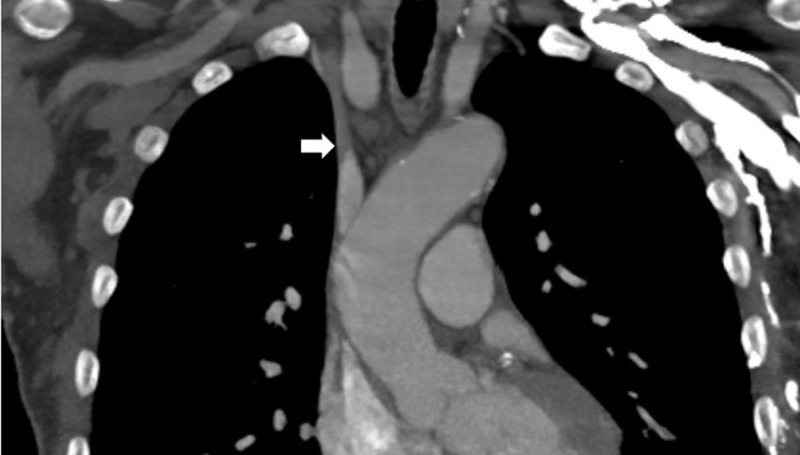

本病例描述了Merit Medical在闭塞的下腔静脉中使用Surfacer®Inside-Out Access Catheter System (SIO)。该手术通常采用右股静脉入路,有急性髂腔血栓形成的禁忌症,因为可能发生栓塞。在病史和影像学检查后,确定该病例的闭塞是慢性的,并决定使用留置导管进行SIO手术。本病例展示了SIO手术在已用尽所有其他选择的中心静脉闭塞患者的某些情况下的应用。

This case describes the use of the Surfacer® Inside-Out Access Catheter System (SIO) from Merit Medical in an occluded inferior vena cava. The procedure typically utilizes right femoral vein access with contraindications of acute iliocaval thrombosis due to possible embolization. After history and imaging studies, the occlusion was determined to be chronic in this case, and a decision was made to employ the SIO procedure using an indwelling catheter. This case demonstrates the use of the SIO procedure in certain settings in patients with central venous occlusions who have exhausted all other options.